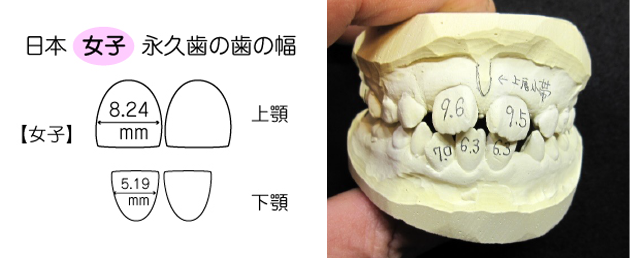

上唇小帯高位付着の経過観察が必要です。

前歯の大きさは、

全体的に、平均値より1.0mm以上 大きい歯になります。

| 場所(部位) | 本人の歯幅径(mm) | 日本人の平均女性 | 差(+・-)mm |

|---|---|---|---|

| 上顎中切歯 | 右側 9.6 左側 9.5 |

8.24mm | +1.36 +1.26 |

| 下顎中・側切歯 | (右側) 中切歯 6.3 側切歯 未萌出 (左側) 中切歯 6.3 側切歯 7.0 |

5.19mm | (右側) +1.11 _ (左側) +1.11 +1.81 |